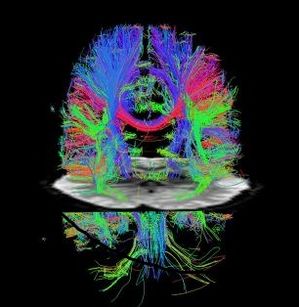

Masticationpedia is a not-for--profit Anglo-Saxon organization, it is a Charity that operates in dental medical research, in particular in the field of neurophysiology of masticatory rehabilitation.

Einstein's metaphor is emblematic: the theory is when we know everything but nothing works. Practice is when everything works but we don't know why. In any case, we always combine theory and practice: nothing works and we don't know why. Basically, this also happens in dentistry where everything doesn't work and we don't know why. Well, Masticationpedia aims to probe the functional properties of the masticatory functions, ranging in various fields of science without prejudices or corporate ideologies to grasp the access key to the system. See video